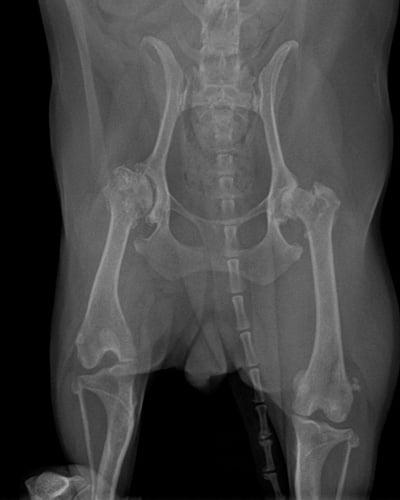

고관절 이형성증은 고관절이 제대로 발달하지 않아 관절의 모양이 비정상적으로 형성되고 관절염이 생기는 질환입니다. 특히 어린 시절에 고관절이 느슨하게 형성된 경우,

시간이 지나며 관절에 과도한 마찰이 생겨 수개월~수년에 걸쳐 관절염이 진행될 수 있습니다. 모든 품종에서 발생할 수 있지만, 특히 대형견에서 흔히 발생합니다.

이 질환은 주로 유전적인 요인으로 인해 발생하며, 관절을 잡아주는 연부조직(인대, 관절낭 등)이 느슨하고, 고관절 주변 근육이 약한 경우, 개가 달리거나 놀 때 대퇴골두가 고관절에서

빠졌다 들어갔다 하게 됩니다. 이 과정에서 연골이 마모되고, 관절이 손상됩니다.